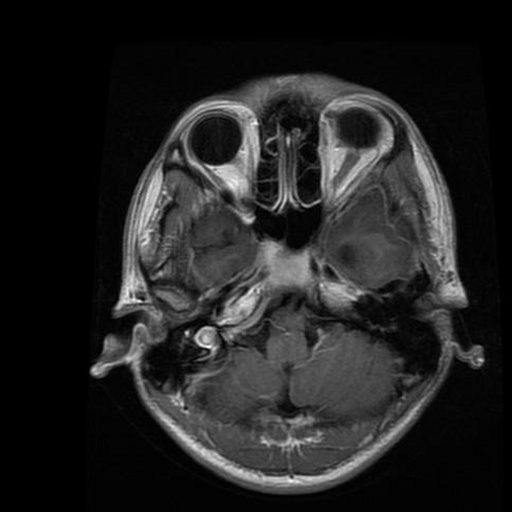

We use the public Brain MRI dataset from Kaggle111https://www.kaggle.com/datasets/masoudnickparvar/brain-tumor-mri-dataset, a widely adopted in the literature for brain-tumor classification. The dataset consists of 2D axial brain MRI slices, provided as raster images with variable spatial resolutions and aspect ratios.

The images were labeled into four categories: no tumor, glioma, meningioma, and pituitary. In the original release, the class counts are no tumor (2000), glioma (1621), meningioma (1645), and pituitary (1757), totaling 7023 images. Table 2 presents the distribution of instances per class along with representative visual examples.

| Class | Quantity | Example |

|---|---|---|

| No Tumor | 2000 | ![]() |

| Glioma | 1621 | ![]() |

| Meningioma | 1645 | ![]() |

| Pituitary | 1757 | ![]() |

| Total | 7023 |